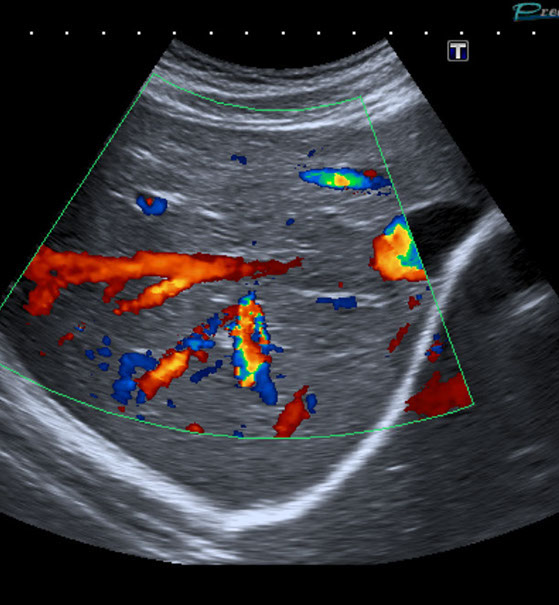

Gefäßultraschall /

Farbdopplersonographie

Die Farbdopplersonographie ist eine zuverlässige Methode zur Beurteilung von Arterien und Venen. Die Farbdopplersonographie kann einerseits Veränderungen der Gefäßwände (z.B. arteriosklerotische Plaques) und dadurch resultierende Engstellen (Stenosen) nachweisen, andererseits durch Blutflussgeschwindigkeitsmessungen den Schweregrad der Stenosen beurteilen. Risikofaktoren für Arteriosklerose und damit für Schlaganfall und Herzinfarkt sind z.B. erhöhte Blutfettwerte, hoher Blutdruck (Hypertonus), Nikotinkonsum.

• Die großen Bauchgefäße (speziell Bauchschlagader) zur Erfassung von Gefäßaussackungen (Aneurysmen) oder Engstellen (Stenosen) sowie bei Verschlüssen, Thrombosen der Pfortader und anderer Bauch- und Beckengefäße.